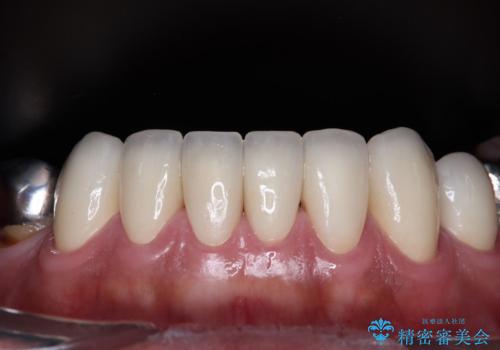

黄ばんだ前歯をきれいに 前歯の審美歯科治療

奥歯の銀歯も気にはなるものの、口を開けたときに目立たないとのことで、上下ともに前歯を中心にオールセラミッククラウンにて補綴治療を行うこととしました。

咬合力が非常に強いため、就寝時には上下ともにマウスピースを使用していただくよう指導をしています。

- かみ合わせや歯ぎしりが強すぎる方はセラミックが割れてしまう可能性があります